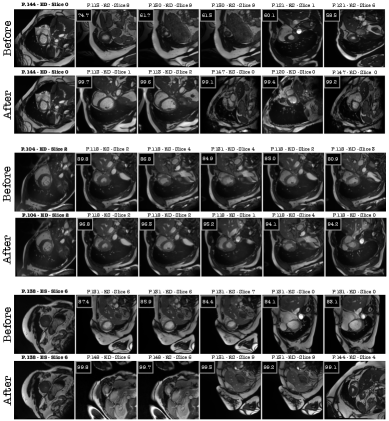

Retrieval Results. Figure 9 illustrates the retrieval performance before and after applying the proposed J-RAS method. The results demonstrate that joint training substantially improves the ability of the retrieval model to identify slices that are anatomically and spatially closer to the query image. For example, in the top two rows, the query image is slice 0 from patient 144. Before joint training, the model retrieved slice 8 from patient 113 as the most similar, which is spatially distant

Refer to caption

from the query slice. After applying J-RAS, the model correctly identified slice 1 from the same patient as the closest match, which is much more consistent with the query slice. The cosine similarity scores shown above each retrieved image also increase significantly, further confirming the improved alignment. Additionally, a similar trend can be seen in the middle rows, where the query image is slice 2 from patient 104. Before J-RAS, the model mistakenly retrieved slice 4 from other patients multiple times, showing poor alignment. After joint training, the retrievals shifted to slices adjacent to the query (slices 0-3), with consistently higher cosine similarity values, reflecting a more anatomically accurate match.

Finally, in the bottom rows, the query image is slice 6 from patient 158. Before J-RAS, retrieved images were often rotated or flipped relative to the query. In contrast, after joint training, the model retrieved images that not only correspond to the same anatomical slice but also preserve the correct orientation, highlighting the robustness of the improved retrieval.

Figure 9: Comparison of retrieved image results using the retrieval model before and after the proposed J-RAS method on patients from the ACDC test set. The first image in each row, with a bold title, represents the query image, while the remaining images are the retrieved results. P.144 denotes patient 144; ES indicates the end-systolic frame, and ED indicates the end-diastolic frame. The cosine similarity between each retrieved image and the query image is shown in a black box at the top-left corner of each image.